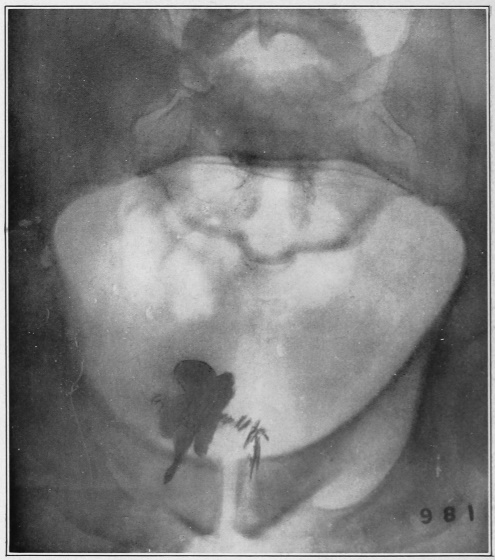

Nine Radiograph Illustrations Showing Mucus Channels and Cavities200

Fig. 4.

1, The dotted lines indicate the normal direction of the anus and rectum; 2, 4, the cavities or pouch formed by dilatation or ballooning from the storage of impacted feces; 3, a probe bent at right angles, and introduced through a speculum, to ascertain the depth of the pouch, which is frequently found to be two and a half inches.